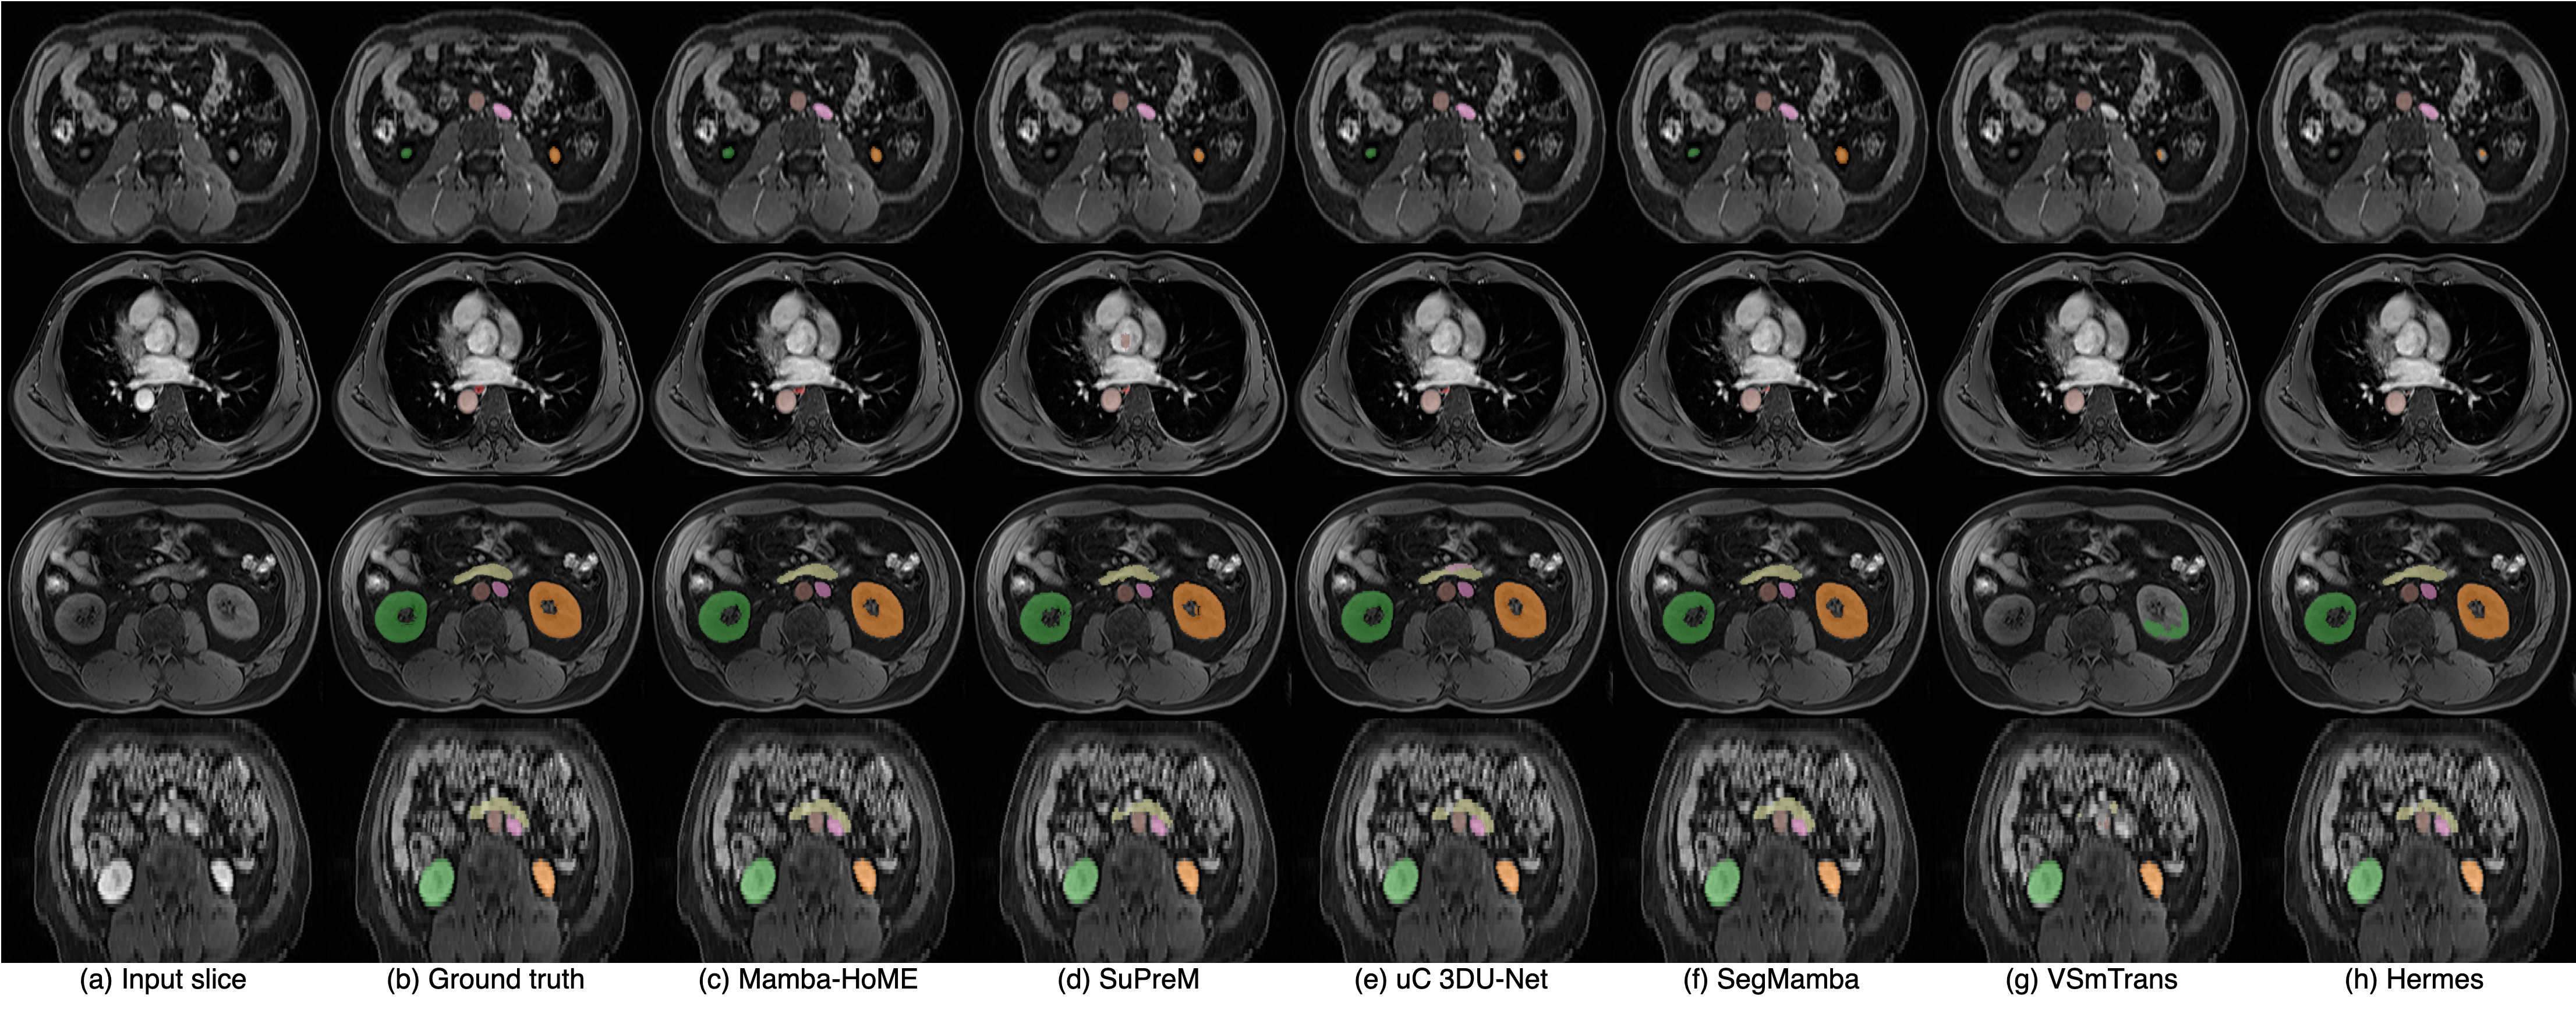

Qualitative results. Figure 2 presents a qualitative comparison of our proposed Mamba-HoME method against the five top-performing baselines across three primary 3D medical imaging modalities: CT, MRI, and US. These modalities exhibit different organ contrasts, noise levels, and resolutions. Mamba-HoME demonstrates consistent improvements in segmentation quality across these scenarios. In the first row, it effectively handles small and closely located structures, showing precise boundary delineation while reducing common artifacts seen in baseline predictions. The second row highlights its capability to accurately segment organs of various shapes and sizes, even under low image quality conditions, with reduced susceptibility to over- or under-segmentation. The third row illustrates Mamba-HoME’s robustness in handling noisy and low-resolution data, maintaining clear and anatomically accurate boundaries.

Figure 2: Qualitative segmentation results from top to bottom: CT, MRI, and 3D US. From left to right, each column shows the input slice, ground truth, the proposed Mamba-HoME, and the five next best-performing methods.